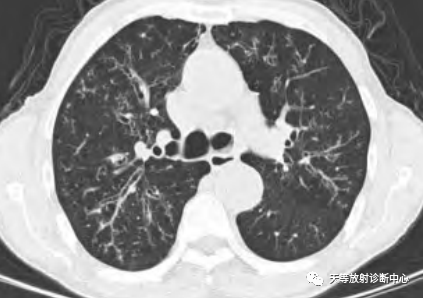

影像学表现:整体观察肺内多发病灶,散在分布,病灶的主要形态为:多发大小不等肺气囊、多发结节共同存在。

1、肺气囊大小不等,张力较大,圆形膨胀感强,周围可见大小不等结节影;

2、病灶主要沿支气管血管束方向分布,部分病灶达到胸膜下;

3、支气管间质增厚;

4、结节影大小不等,小的呈树芽征堆积,大的部分到达胸膜小,具有糊墙征,性格较温和。仔细观察病灶呈四边形、多边形,边缘刀切感,边界模糊。